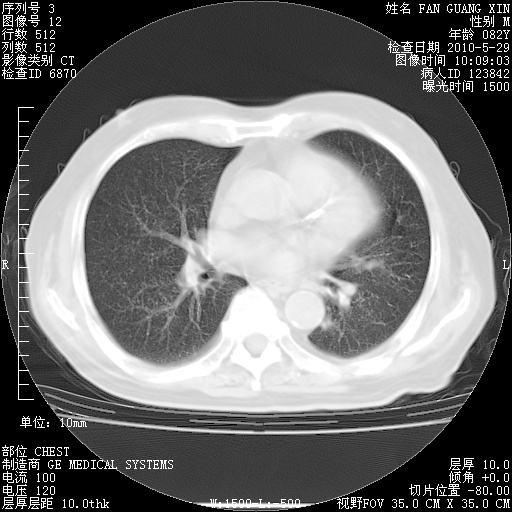

再治疗10天后的肺部CT

阅读此次胸部CT,肺间质渗出性改变较入院时有吸收。目前从体温、白细胞、中性分叶明显增高,肯定存在细菌感染(发生医院感染哦,若无消化道及泌尿系统等感染的依据,肺部感染可能大)。若你院头孢哌酮舒巴坦钠耐药率较高,同意你的方案,若48小时体温仍高,可考虑使用碳青霉稀类抗菌药物,同时可予超声雾化、注意滴数时加大液体量。白蛋白33.30g/L较低哦,需加强营养等支持治疗。